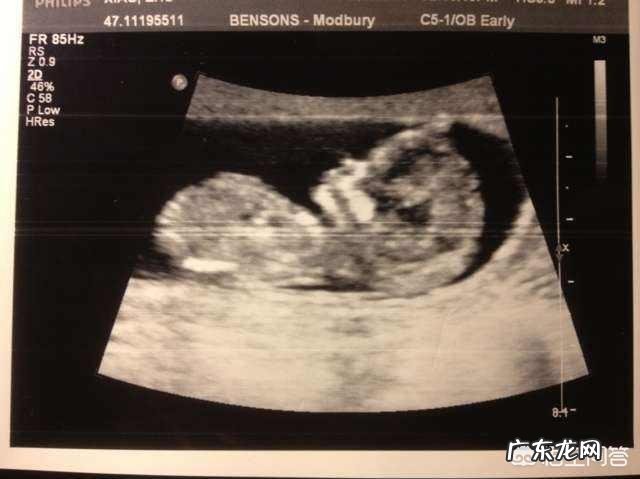

在孕期医生都会通过B超检测胎儿各个器官发育情况 , 以此来判断胎儿发育是否达标 。由于测量手法、角度不同 , 有时候也会出现些许误差 , 但这都属于正常现象 , 而且在医学上允许出现上下两周的误差 。

1、胎儿发育标准:身长约有16cm;

重约110g;

双顶径平均值为3.62±0.58cm;

腹围平均值为10.32±1.92cm ,

【怀孕四个月B超准吗?】股骨长约2.10±0.51cm 。

2、胎儿五官:脸部已经出具人的轮廓和外形 , 在B超显示下 , 看起来更像一个小娃娃了 。眉毛和头发也生长出来了 , 不过量特别稀少 , 孕妈不需要担心 , 等到七个月的时候还会再次发育 。